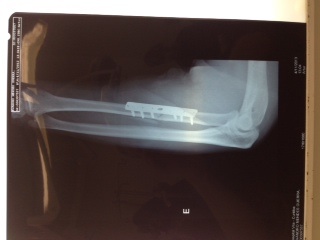

Olha ai a minha foto depois do Enduro Fim da Fazenda.

Tibia, fratura, haste, parafusos,

Já são 2,5 meses de molho.

Vc não ta sozinho. kkkkkkkkkkk